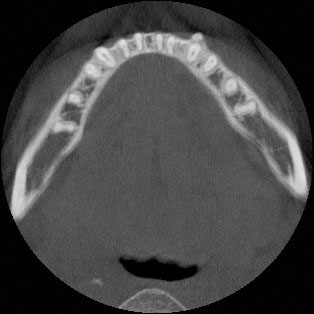

Une patiente de 27 ans présentant une malocclusion de classe III, un encombrement de 15 mm de l’arcade supérieure, une béance antérieure, une occlusion croisée latérale et un score ABO total de 29. Le profil facial était droit avec un maxillaire rétrusif. Les incisives supérieures et inférieures étaient rétroclinées. Un manque extrême de soutien du milieu du visage a été constaté. Des arcades dentaires rétrécies ont conduit à un sourire étroit et à des couloirs buccaux sombres. Aucune investigation myofonctionnelle n’a été réalisée, car le sujet n’était pas considéré à ce moment-là. Le Dr Coca a commencé à travailler sur la base de la philosophie de Damon en 2016. Pour le Dr Coca, ce cas présentait une courbe d’apprentissage, c’est pourquoi il pense qu’il est important de partager sa propre expérience, dans l’espoir que d’autres collègues lisant cet article bénéficient d’une meilleure expérience.

Étant donné le principe orthodontique du visage d’abord, l’objectif principal était d’augmenter le soutien du milieu du visage. Pour y parvenir, il a fallu développer le maxillaire supérieur, corriger l’occlusion croisée et aligner les dents. La fermeture de la béance était un objectif secondaire.

Le traitement ayant débuté en 2017 et le patient préférant une option de brackets moins visible, des brackets Damon Clear ont été utilisés. Des canines supérieures à couple élevé et des incisives supérieures à faible couple ont été choisies afin d’offrir le meilleur contrôle du couple pour le développement de l’arcade supérieure. Pour l’arcade inférieure, il n’y avait pas d’informations sur les autres possibilités de brackets. Des rampes de morsure ont été appliquées sur les deuxièmes molaires supérieures.

Les dents sont en très bonne position et l’os s’est remodelé.